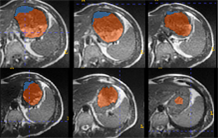

Focus sur l'imageur 7T préclinique de NeuroSpin équipé d’un dispositif non invasif de perméabilisation temporaire de la barrière hémato-encéphalique par ultrasons focalisés pour suivre la délivrance de médicaments dans le cerveau de modèles rongeurs.